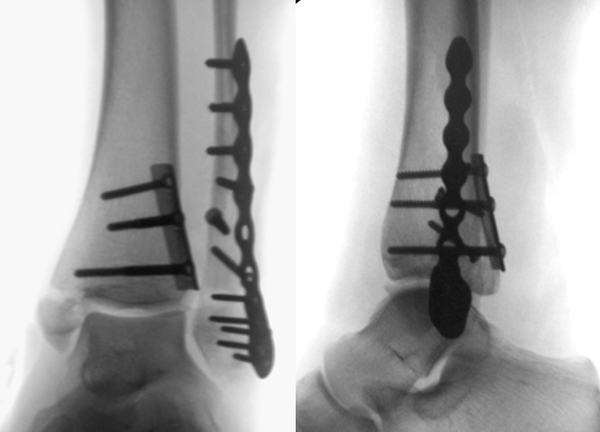

Luxationsfrakturen (Abbildung 7) sollten unter i.v.-Analgesie so schnell wie möglich reponiert werden, um Haut- und Weichteilschäden, Störungen der Durchblutung und Sensibilität, sowie den durch die Fehlstellung bedingten Druck auf den Knorpel zu verringern. Anschließend erfolgt die Ruhigstellung in einem gespaltenen Unterschenkelgips. Offene Frakturen, geschlossene Frakturen mit kritischen Weichteilverhältnissen, sowie hochgradig instabile Frakturen, die sich unter entsprechender Analgesie nicht zufriedenstellend reponieren bzw. retinieren lassen, stellen eine Notfallindikation dar. In diesen Fällen sollte die Anlage eines Fixateur externe erfolgen (Abbildung 8). Die definitive Frakturversorgung erfolgt zweizeitig nach entsprechender Konsolidierung der Weichteile. Eine Kompartment-Spaltung ist bei OSG-Frakturen nur sehr selten erforderlich.

Die Versorgung von AO 44-B Frakturen erfolgt über einen längsverlaufenden lateralen Zugang. In der Regel gelingt eine suffiziente Stabilisierung mittels interfragmentärer Zugschraube (bei langem Frakturverlauf ggf. 2 Zugschrauben) und einer zusätzlichen Neutralisationsplatte (Abbildung 9 & 10).

Bei multifragmentären Frakturen (AO 44-B2.3) oder bei schlechter Knochenqualität sollte die Versorgung mittels winkelstabiler Plattenosteosynthese erwogen werden (Abbildung 11 & 12).

Frakturen vom Typ AO 44-C werden in der Regel mittels interfragmentärer Zugschraube und Neutralisations-Plattenosteosynthese versorgt. Die Versorgung von Frakturen mit metaphysärer Trümmerzone (AO 44-C2) ist mitunter anspruchsvoll. Entscheidend ist die Wiederherstellung der korrekten Länge und Rotation der Fibula. Die Verwendung von winkelstabilen Implantaten bietet hier eine höhere Stabilität. Bei Typ C Verletzungen liegt definitionsgemäß eine Syndesmoseninsuffizienz vor, die entsprechend versorgt wird (siehe Abschnitt Syndesmoseninsuffizienz). Bei hohen Fibulafrakturen (AO 44-C3, Maisonneuve-Frakturen) steht die Versorgung der Syndesmoseninstabilität im Vordergrund. Eine zusätzliche Versorgung der proximalen Fibulafraktur ist nicht erforderlich.

Liegt eine Syndesmosen-Insuffizienz vor (Abbildung 18), so erfolgt nach der Osteosynthese aller Frakturen im ersten Schritt die Reposition der Fibula in die Incisura fibularis der Tibia mittels Repositionszange. Danach sollte geprüft werden, ob die Dorsalextension im OSG noch uneingeschränkt möglich ist. Falls vorhanden, ist es hilfreich die korrekte Reposition mittels intraoperativen CT zu kontrollieren. Die Durchführung eines intraoperativen 3D Scans konnte nach zufriedenstellenden Ergebnissen in der konventionellen 2D Bildgebung bereits intraoperativ in 20-40% ein korrekturbedürftiges Ergebnis zeigen 3132. Anschließend erfolgt das Einbringen einer Stellschraube oder eines Tight Ropes (Abbildung 19). Dabei sollte darauf geachtet werden, dass die Bohrung knapp proximal des distalen Tibio-Fibular-Gelenkes angelegt wird. Die Bohrung sollte in 30° von posterior nach anterior und parallel zur Gelenklinie des OSG gerichtet sein. Beim Einbringen der Schraube ist darauf zu achten, die Fibula nicht an die Tibia zu komprimieren. Postoperativ empfehlen wir die Durchführung einer CT-Untersuchung des verletzten und des unverletzten Sprunggelenkes. Nur so ist aus unserer Sicht die Reposition der Fibula sicher zu beurteilen.